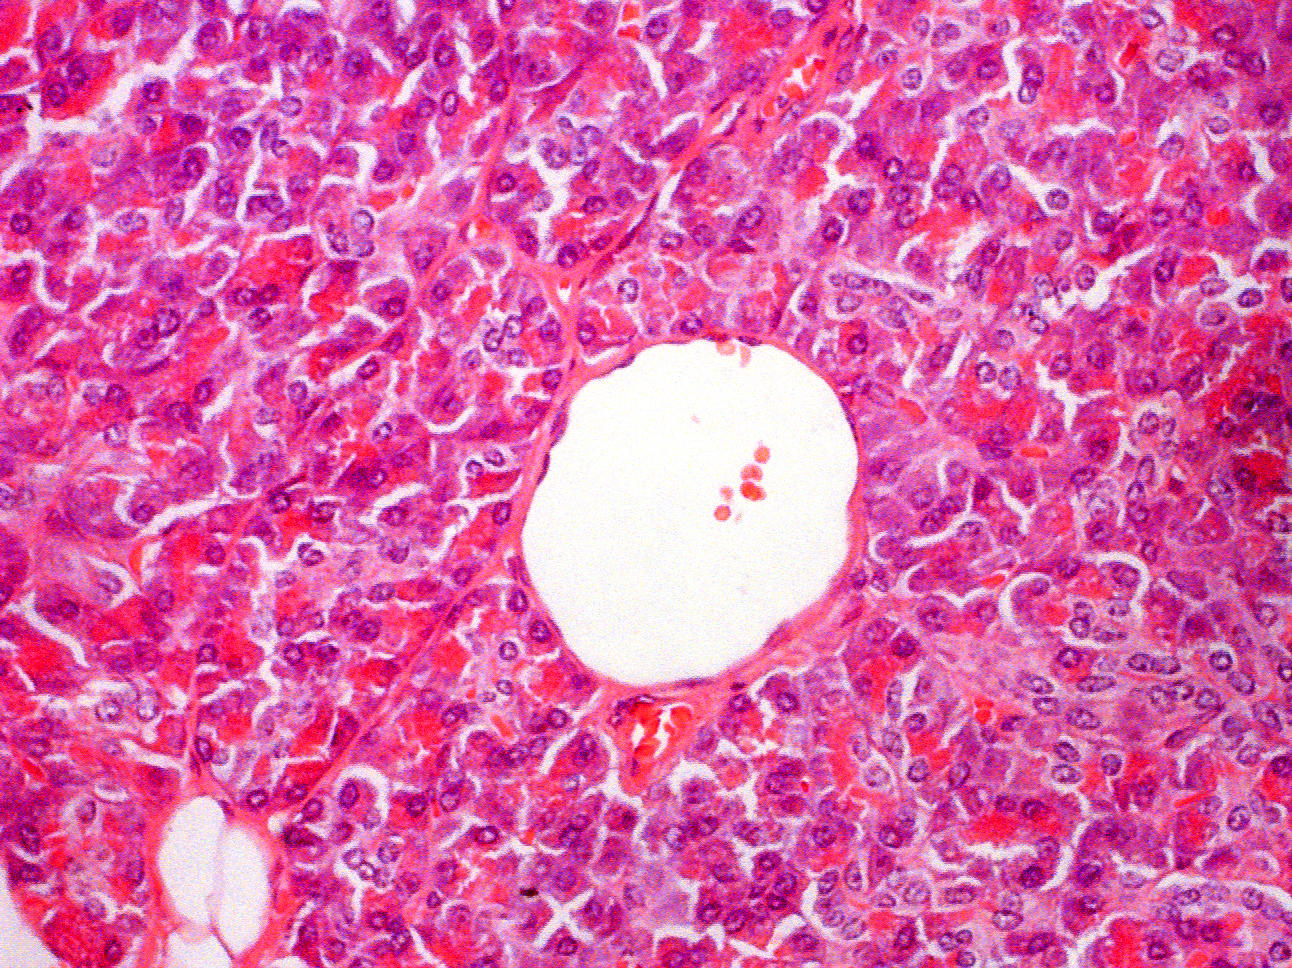

Small blood vessel vs Fat cells

Blood vessel are lined with endothelium. Several squamous cell nuclei line the lumen of the blood vessel. In this capillary, several red blood cells are also present in the lumen. This is not always the case. A very thin intimal layer can be seen. Compare the tissue slide with the drawing of a small artery and vein below.